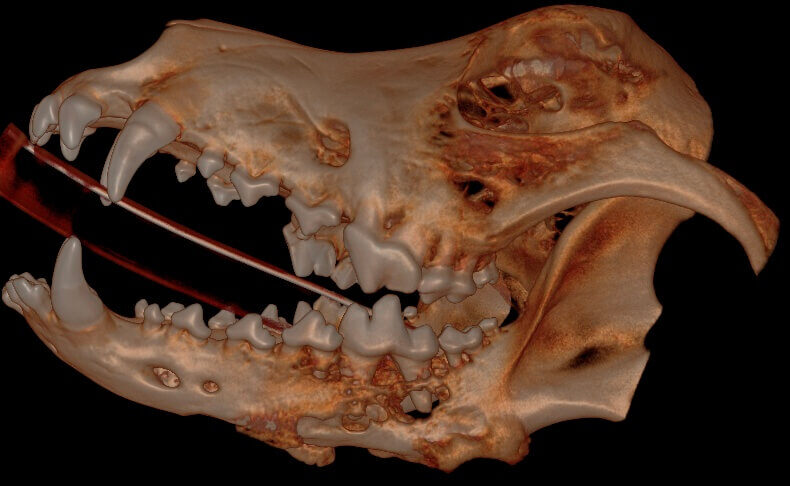

Below: 3D Hard Tissue Overview (left side)

.jpg?width=790&height=486&name=3D%20Hard%20Tissue%20Overview%20(left%20side).jpg)